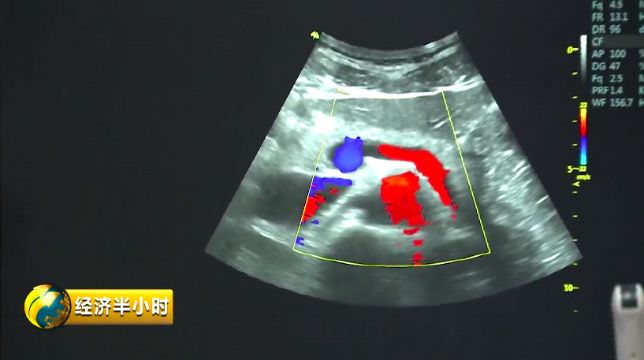

彩色B超

有一个特殊的彩色B超设备,不仅能够精确诊断,还能帮助大夫有效地给予患者治疗。也就是说,在治疗疾病时,在超声波的介入下,药物被精准送达病变位置,释放药物,从而实现靶向治疗。而且这个彩色B超设备副作用很少,安全性特别好。央视财经《经济半小时》记者在苏州工业园区了解到,目前这种彩色B超设备在国际上已经达到一流水平。